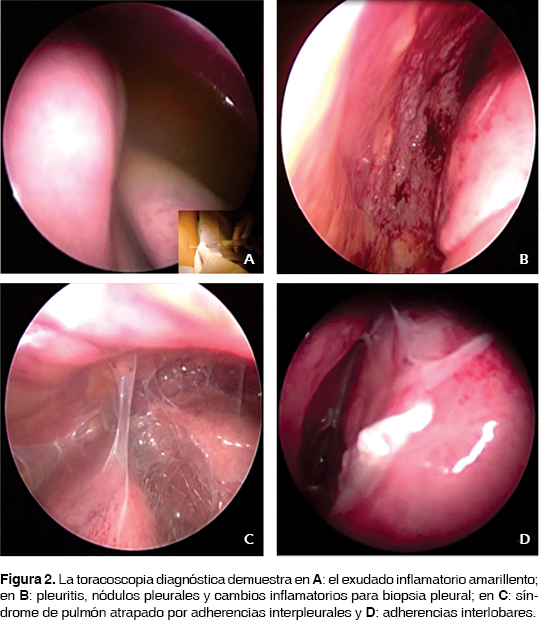

La actividad lúpica fue tratada prontamente con metilprednisolona en altas dosis, gama globulina intravenosa y rituximab sin mejoría alguna; fueron corregidos estados trasudativos de hipoalbuminemia, sobrecarga hídrica e hiponatremia. Bajo este panorama es considerado derrame pleural masivo, bilateral y refractario a manejo conservador, se realiza tratamiento quirúrgico con drenaje pleural y adherensiolisis del pulmón izquierdo atrapado con toma de biopsia pleural y pleurectomía parcial con pleurodesis química con yodo povidona al 1% por toracoscopia videoasistida. Del hemitórax derecho, una vez descartado por toracoscopia la presencia de un pulmón atrapado y confirmando la expansión pulmonar, se decidió instilar bajo visión pleurodesis química con yodo povidona al 1% y pinzamiento por cuatro horas de la sonda pleural (figuras 2 y 3). Se instiló vía intrapleural por tubo de toracostomía derecha y una sesión más con yodo povidona sin complicaciones. Con evolución satisfactoria fueron retirados los drenajes pleurales al tercer y cuarto día y documentadas la expansión pulmonar clínica y radiológica; y sin recurrencias a dos años de vigilancia y tratamiento médico inmunosupresor. El reporte histopatológico documentó pleuritis aguda y crónica inespecífica mayormente acentuado alrededor de los vasos sanguíneos, con hiperplasia mesotelial e infiltrado linfoplasmocitario. La citología del líquido pleural mostró células mesoteliales reactivas mezcladas con linfocitos.

La reducción en los niveles de complemento en líquido pleural permite diferenciar a los derrames de otras enfermedades del tejido conectivo. Los ANA con títulos > 1:160 en líquido pleural y la relación de anticuerpos ANA pleural: séricos > 1 son sugestivos, pero no diagnósticos de pleuritis lúpica.1-2,15 Ocasionalmente, las células de lupus eritematoso son encontradas en los derrames serosos de la pleuritis lúpica, aunque inespecíficas pues pueden referirse en los derrames malignos y en artritis reumatoide. La toracoscopia revela nódulos en la pleura visceral, y las biopsias pleurales sometidas a inmunofluorescencia muestran en estos nódulos depósito de inmunoglobulinas.16,17 En ausencia de actividad lúpica, los derrames pleurales pequeños, unilaterales y con leve dolor pleurítico pueden responder a agentes antiinflamatorios no esteroideos.1-3 La terapia con corticosteroides sistémicos es la piedra angular del tratamiento en la pleuritis lúpica.1,2,18 En los derrames pleurales masivos y refractarios a las altas dosis de esteroides se han utilizado cursos mensuales de ciclosporina y la combinación con inmunoglobulina intravenosa es referida como benéfica en la población adulta.1,2,18,19 El manejo a largo plazo puede involucrar el uso de antimaláricos como la hidroxicloroquina. En adultos se han reportado la pleurodesis con tetraciclina y con talco, así como la pleurectomía parcial o total en el tratamiento quirúrgico de estos pacientes refractarios al manejo inmunosupresor, inclusive se han considerado como opciones tempranas y definitivas de manejo.1,2,20-22